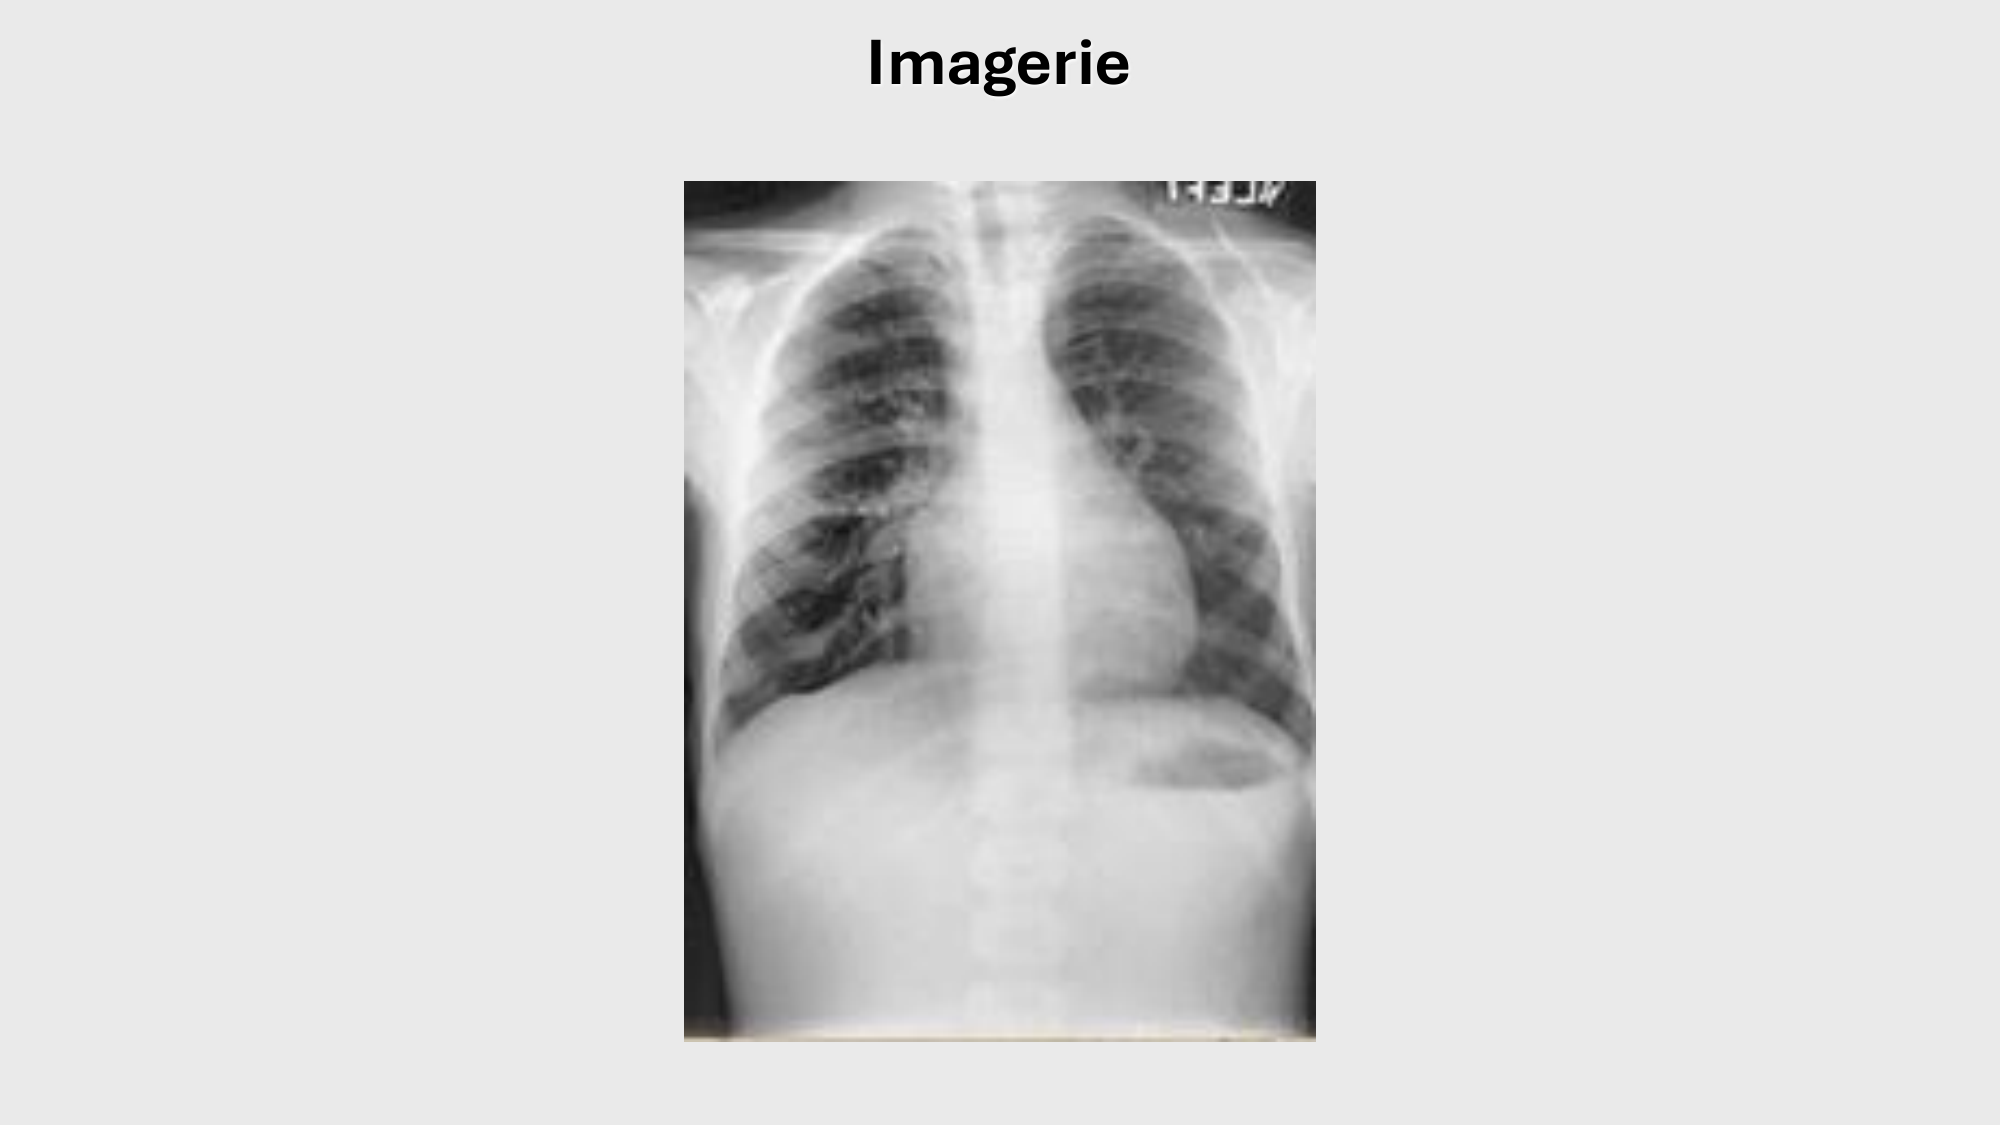

01.12 · F-Mach-Cas de-liaison-Athero-1-2025

F-Mach-Cas de-liaison-Athero-1-2025

Atherosclerosis series · 61 pages · 8 sections